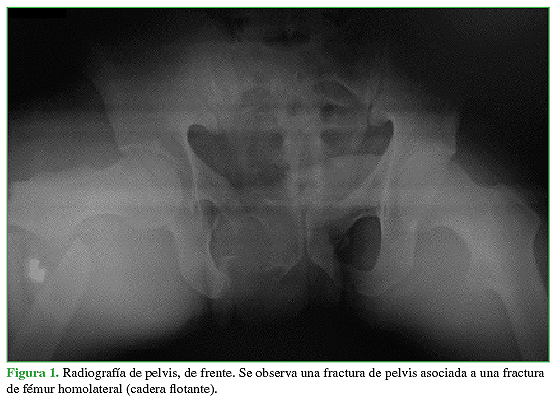

El término “flotante” relacionado con alguna articulación indica una disrupción esquelética por encima y por debajo de ella, que puede ser intrarticular o extrarticular. Este término fue introducido por Blake y McBryde, en 1975, para describir la rodilla flotante.1 En nuestro caso, nos referimos a una situación poco común en la que están involucradas una fractura de fémur con una fractura de pelvis o de acetábulo homolateral y que requerirán un tratamiento quirúrgico específico en forma secuencial (Figuras 1y 2).2

Se incluyó a 102 pacientes con trauma de pelvis o acetábulo reunidos en dos grupos según la presencia de CF (CF: 23 pacientes, pelvis/acetábulo: 79 pacientes). En la Tabla 1, se resume la descripción global de la muestra.